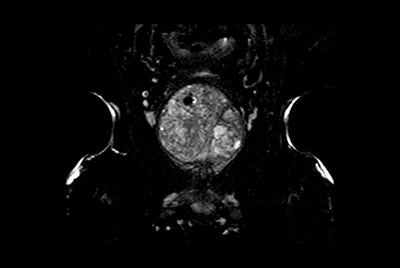

Multi-phase, contrast-enhanced prostate imaging